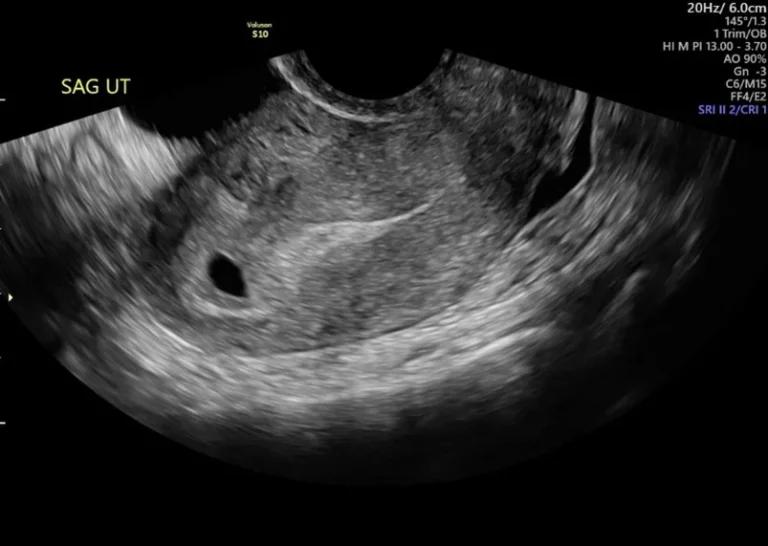

Prenatal ultrasound

Cleft lip and palate may sometimes be detected using ultrasound scans during pregnancy. This scan is usually done at between 18 and 22 weeks of pregnancy. Cleft lip detection is easier to identify because of the visible physical changes in the baby’s face. A cleft palate alone (without a cleft lip) is sometimes challenging to see.

If detected, parents are counselled regarding the condition and the family may also be referred for genetic counselling and other tests. At this stage your healthcare provider may recommend amniocentesis to check for associated genetic conditions. Amniocentesis is a procedure to remove amniotic fluid from the amniotic sac.